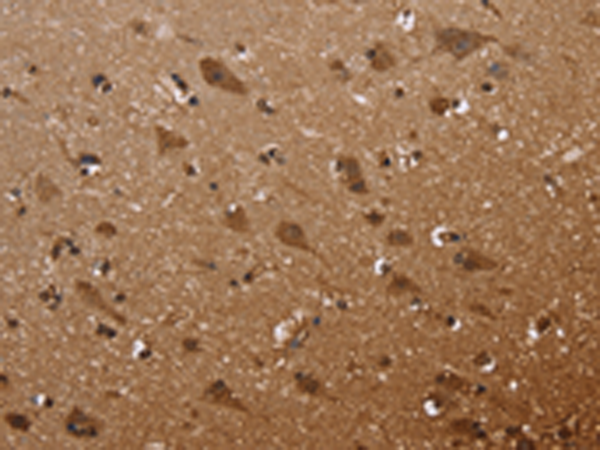

分类: 科研抗体货号: P08315别名: MLC-B; MRLC2应用: WB,IHC反应种属: Human, Mouse, Rat

分类: 科研抗体货号: P08296别名: HSCO; YF13H12应用: WB,IHC反应种属: Human, Mouse

分类: 科研抗体货号: P08308别名: DRR1; TU3A应用: IHC反应种属: Human

分类: 科研抗体货号: P08314别名: MLSTD1; SDR10E2应用: WB,IHC反应种属: Human, Mouse

分类: 科研抗体货号: P08294别名: ET1; PPET1; HDLCQ7应用: IHC反应种属: Human

分类: 科研抗体货号: P08307别名: PKB; PTK; CAKB; FAK2; PYK2; CADTK; FADK2; RAFTK应用: WB,IHC反应种属: Human, Mouse, Rat

分类: 科研抗体货号: P08313别名: FAPA; SIMP; DPPIV; FAPalpha应用: WB,IHC反应种属: Human, Mouse

分类: 科研抗体货号: P08292别名: endocan应用: IHC反应种属: Human

分类: 科研抗体货号: P08306别名: LFG; LFG2; NGP35; NMP35; TMBIM2应用: WB,IHC反应种属: Human, Mouse, Rat

分类: 科研抗体货号: P08311别名: FAF应用: IHC反应种属: Human